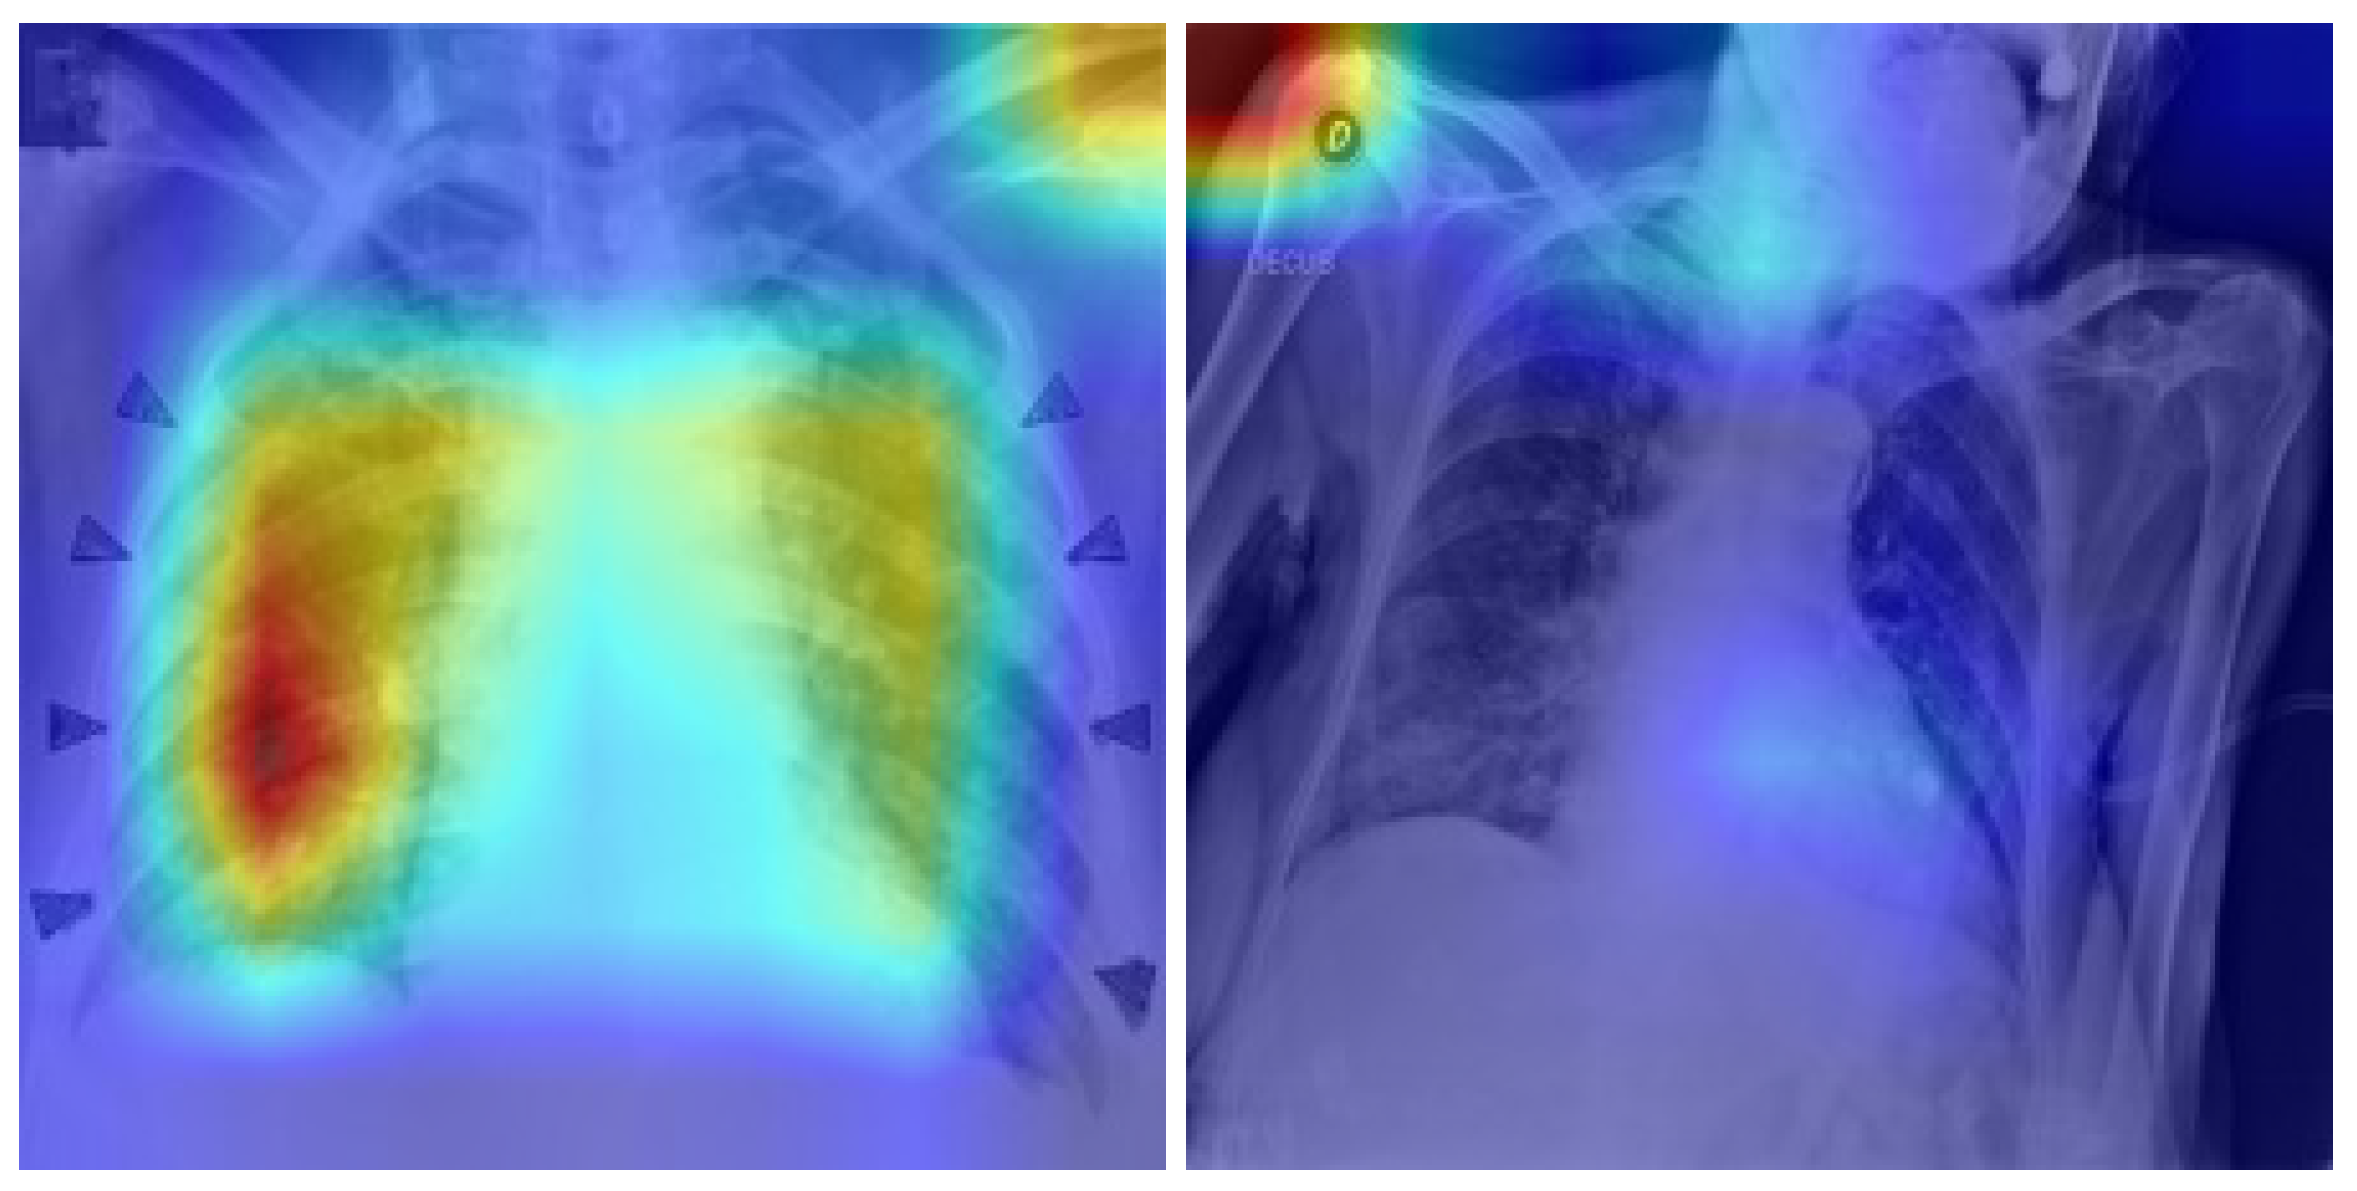

As illustrated in Figure 6, the Grad-CAM process begins by finding the last convolutional layer of the trained model. Gradients of the predicted class are utilized to weight the feature maps of the same layer. The result is a heatmap of the salient regions, which is overlaid on the original chest X-ray.

For qualitative assessment of model attention across different prediction types, we selected one representative image per true positive (TP), true negative (TN), and false negative (FN) case. There were no false positives (FP) predictions in this test set; hence, that cell is marked as N/A. Figure 7 shows that the model tends to focus on the lower or peripheral regions of the lung in cases of COVID-positive, as documented radiographic patterns.

Correct vs. Incorrect Attention Patterns

Figure 16 shows the extreme difference between adequate and inadequate attention patterns in COVID-19 patients. The left image is a true positive (TP) prediction where the model correctly diagnoses the chest X-ray as COVID-19, and the Grad-CAM heatmap is centered around the lower and peripheral lung zones—regions previously known to be radiologically significant for COVID pathology.

On the other hand, the incorrect image shows a false negative (FN), where a COVID-positive image was misclassified as Normal. In this instance, active areas in non-germane areas of the anatomy, i.e., the shoulder and upper chest, are shown through Grad-CAM visualization. This mismatch suggests that the model either overlooked implicit pulmonary clues or was misled by image artifacts. These trends affirm the need for explainability in AI diagnosis and why agentic decision-making layers must be employed to indicate uncertain or risky errors.

In general, Grad-CAM heatmaps suggest that the model had learned to focus radiologically important regions—particularly lower lung lobes in COVID-positive samples—without spurious activation in normal cases. Consistency with clinical expectation boosts confidence in the model’s decision and provides a foundation for GPT-based agentic reasoning integration, as discussed in the next section.

Figure 6. Grad-CAM pipeline applied with the EfficientNet-B0 model trained. The penultimate convolutional layer is used to compute attention heatmaps for each prediction.The color gradients (red–yellow–blue) represent attention intensity, where red indicates regions of higher model focus and blue indicates lower attention.

Figure 7. Prototype Grad-CAM visualizations for TP, TN, and FN samples. The blank FP panel is intentional, as no false-positive cases occurred in this test set. Red/yellow areas indicate high model attention.